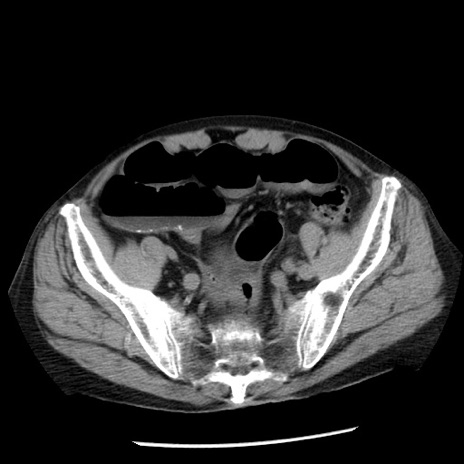

症例26(横断像)

【症例】80歳代男性

【主訴】嘔吐

【現病歴】昨晩2回嘔吐あり、今朝になっても嘔吐あり。来院。

【既往歴】胃潰瘍

【身体所見】意識清明、BT 37.6℃、BP 166/95mmHg、HR 100bpm、SpO2 97%、腹部:平坦・軟、腸蠕動音聴取良好、圧痛なし。

【データ】WBC 21900、CRP 1.46